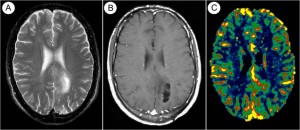

Il team di ricercatori della QMRI Tech è esperto di studi di neuroimaging mediante tecniche RM di Perfusione con mezzo di contrasto (DSC e DCE MRI), Diffusione (DWI e DTI), IVIM, Spettroscopia, fMRI Bold, Rilassometria, Texture Analysis.